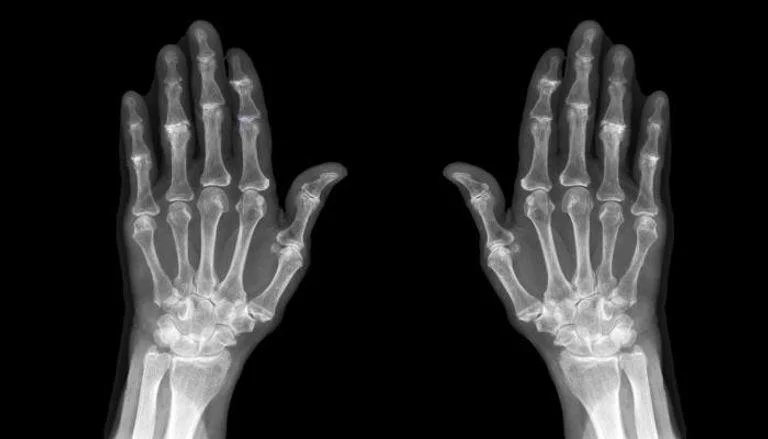

يعاني عدد كبير من الأشخاص من هشاشة العظام وتزداد نسب الإصابة به بين من هم أكبر سنا والنساء وهو من أكثر الأمراض الصامتة التى لا تظهر أعراضا واضحة إلا بعد التمكن من جسد المريض.